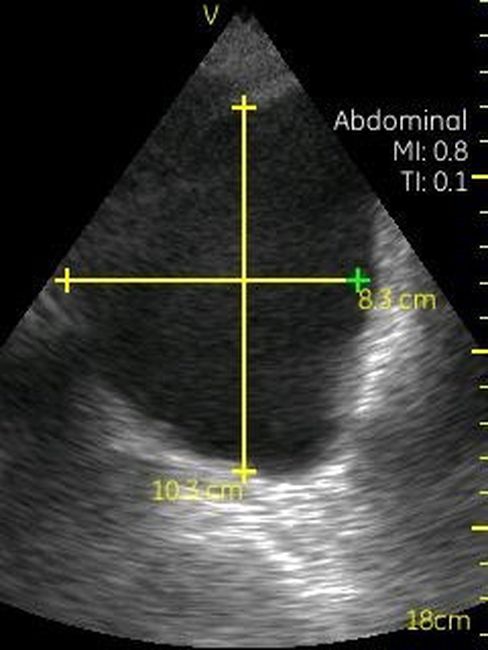

Визуализация Vscan:

· Черно-белый режим для визуализации анатомических структур в реальном времени.

· Поле зрения в черно-белом режиме: до 75 градусов с максимальной глубиной 25 см.

Размеры и вес:

· Дисплей: 135×73×28 мм.

· Датчик: 120×33×26 мм.

· Вес (весь прибор целиком): 390 г.

· Дисплей: 3,5 дюйма, разрешение — 240×320 пикселей.